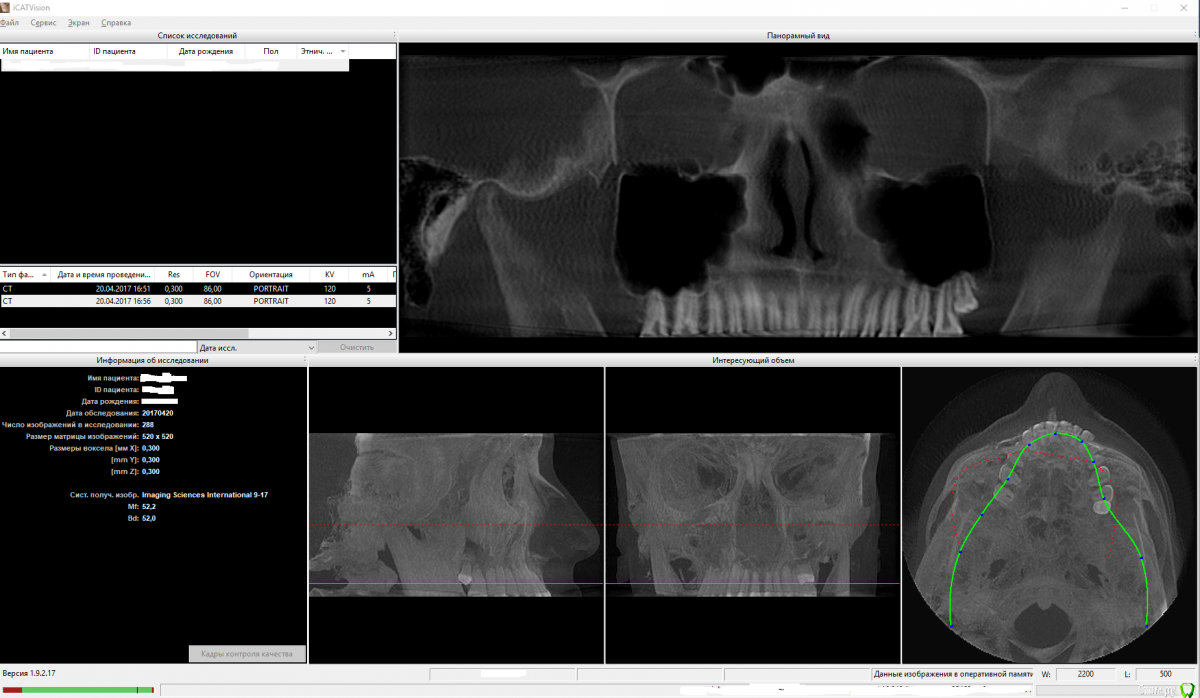

Ness Опубликовано 23 апреля, 2017 Поделиться Опубликовано 23 апреля, 2017 Добрый вечер! Сыну в феврале исполнилось 17 лет. В конце весны прошлого года стали интенсивно расти нижние восьмерки. Каюсь, недоглядел. Каким-то непостижимым образом за год нижняя челюсть сильно выдвинулась настолько, что ему стало тяжело есть и значительно ухудшилась дикция.Пошли к ордотонту, который немедленно порекомендовал удалить эти восьмерки, что и было сделано. Далее, консультировались у трех разных ортодонтов и двух челюстно-лицевых хирургов.Первый ортодонт (который собственно и сказалал удалять восьмерки) порекомендовал удалить нижние четверки и попытаться брекетами сдвинуть зубы несколько назад. Но, как мы с сыном поняли, проблему это не устранит, т.к. нижняя челюсть то останется выдвинутой.Двое остальных ортодонтов сказали - без вариантов только хирургия.Настала очередь консультироваться у хирургов. Сделали КТ.Здесь мнение хирургов разделилось. Один рекомендует ТОЛЬКО укоротить нижнюю челюсть и задвинуть её. Второй говорит, что верхняя челюсть недоразвита и двигать нужно ОБЕ ибо если подвинуть ТОЛЬКО нижнюю, то через несколько лет она опять выдвинется вперед.Мы с сыном в полном затруднении. Перелопатили массу информации, но разобраться тяжело. Прошу помощи советом у профессионалов - как наиболее целесообразно поступить в данной ситуации?Из программы (которую нам дали вместе с диском) ICatvision я сделал два снимка экрана нижней и верхней челюсти (файлы .dcm в наличии есть, но пока я их, согласно правилам, никуда не выгружаю без дополнительных требований со стороны врачей) и прикрепил к сообщению здесь.Также на следующей недели пообещали дать еще .dcm файлы (обработанные), которые нужно будет просматривать другой программой - SimPlant O&O Viewer.Но может можно на основании тех данных что уже есть подсказать нам какое решение в нашей ситуации будет более предпочтительным? Операции, конечно, боимся. Но сын морально готов, лишь бы это убрало проблему с прикусом, речью, жеванием, дыханием и пр.Заранее спасибо большое за уделенное время! Ссылка на комментарий